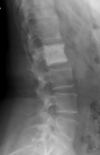

Fratura compressiva da coluna lombar

Causa achatamento do corpo e acunhamento geralmente anterior.

Tipo mais comum de fratura da coluna lombar

Estável.

Mecanismo flexão anterior ou lateral